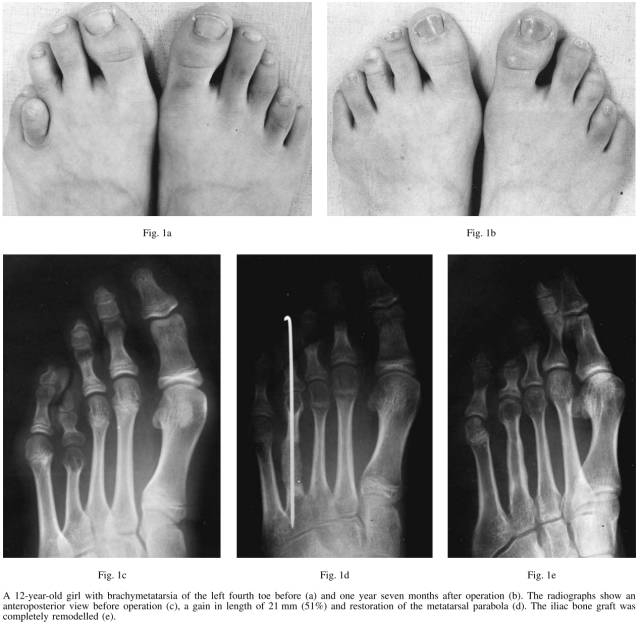

在1989年到1995年,我们在21例患者41例足趾,其中跖骨34例,近节趾骨7例。为了获得理想的长度,其中跖骨短小的患者有6例也进行了趾骨延长。所有的患者都是女性,平均年龄在16岁,10到36岁不等。所有的病人抱怨外观不好看,其中有10例伴有行走时相邻的跖骨头疼痛。有11例患者双边受到影响,其中第四跖骨短小10例,第一跖骨短小1例。在10例双边影响6例是第四跖骨,2例是第一和第四跖骨,一例是第一第三第四跖骨。在19例患者中,我们使用了髂骨植骨。在两例双边第一和第四短小,我们短缩了第二和第三跖骨,把骨块填塞到第四跖骨。3例患者有家族史,四例同时伴有手指短小,其中2例是双手,2例是同侧手。术后随访平均2.1年,从1到6.5年不等。

背侧纵行切口,锐性分离骨间肌。伸肌健分离开,暴露出短小的跖骨,从跖骨中段横断,1.14 or 1.57mm纵穿到末节趾骨,这是为了防止跖趾关节和趾间关节在延长的过程中的半脱位。我们逐步撑开20-30分钟逐步延长,降低软组织的张力。通常一次性延长可以轻易达到7-8毫米。逐步撑开延长一次大约延长接近1.5毫米,维持3分钟。自体髂骨取出后克氏针固定到远近端跖骨或者跗骨之间。

膝下行走石膏固定,石膏和克氏针在术后7-10周去除(拍片先确诊是否愈合),术后12周允许负重行走。近节趾骨延长和此类似。

我们的逐步延长技术通过逐步的持续放松的拉力延长20-30分钟,然后达到需要的长度21毫米,每次延长1.5毫米固定3分钟左右,不需要Z字延长肌腱和VY推进皮肤,没有发生血管神经的问题。

牵张成骨是通过外固定架的逐步延长,我们是通过术中逐步撑开获得满意的长度。我们通过对截骨处持续撑开20-30分钟包括周围的组织。在34例跖骨中通过我们的方法获得了平均14毫米延长,和牵张成骨的长度差不多,牵张成骨13-15毫米。牵张成骨会有关节半脱位,虽然可以通过纵行克氏针固定减少并发症。我们研究中没有发现跖趾关节半脱位。